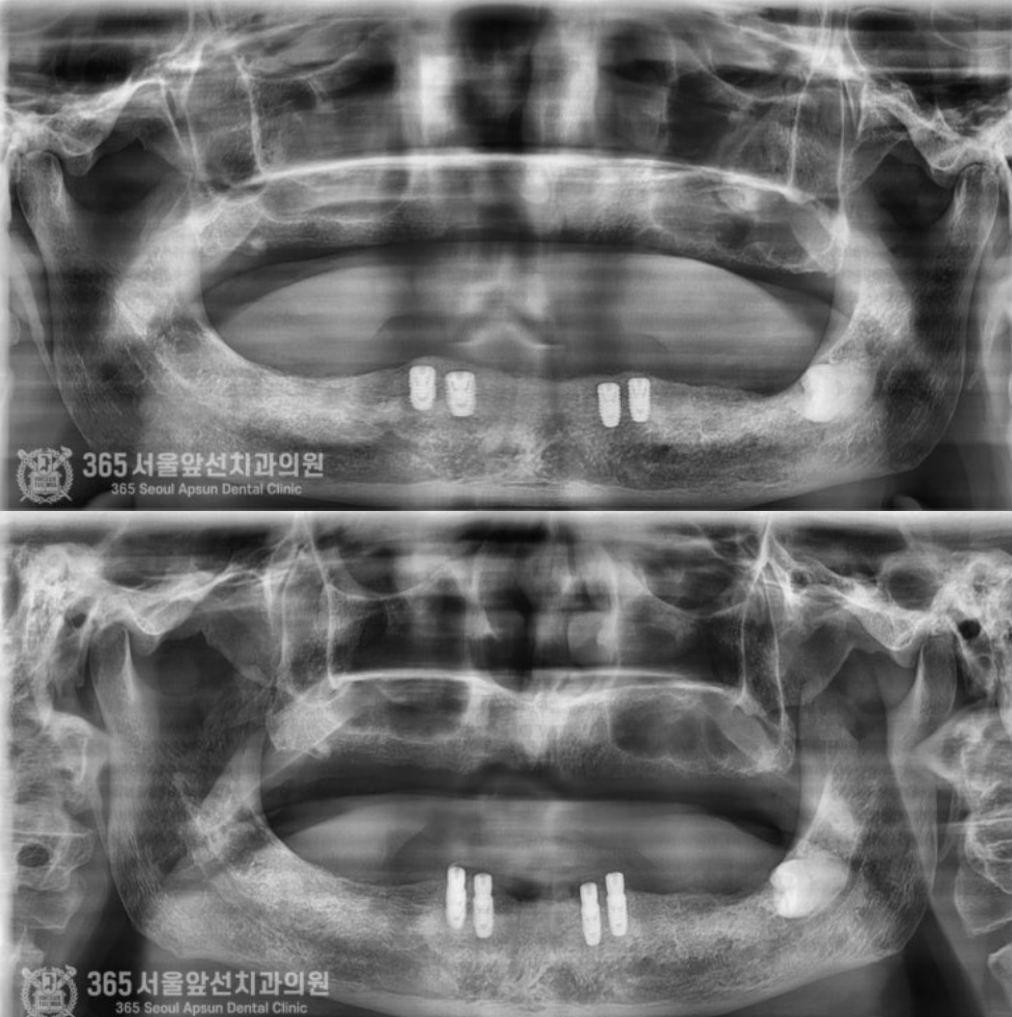

촬영일시 : 2024.05.14 임플란트가 잘 식립된 사진입니다. 추후 아래 틀니를 붙잡아줄 중요한 녀석들이죠 ㅎㅎ 이렇게 심어놓고 뼈와 임플란트가 붙을때까지 시간을 기다려줍니다.

촬영일시 : 2024.06.14 기다리는 과정에서 문제가 없는지 체크도 꼼꼼히 합니다. 문제 없이 잘 진행되어 가고 있네요 좋습니다ㅎㅎ 이제 시간이 지나서 임플란트가 뼈와 단단하게 붙었다고 판단되기에 본을 뜨기 위한 단추를 달아줍니다. 전문적인 용어로는 2차 수술이라고 하는 과정입니다. (윗 부분 사진) 아랫부분 사진을 보시면 임플란트가 뼈와 단단하게 붙었구요. 이제 본을 뜨기 위해 단추를 달아줍니다ㅎㅎ 이제 거의 다와갑니다. 단추를 달아주고 본을 떠서 아래 틀니를 붙잡아줄 튼튼한 임플란트 브릿지를 먼저 만듭니다.